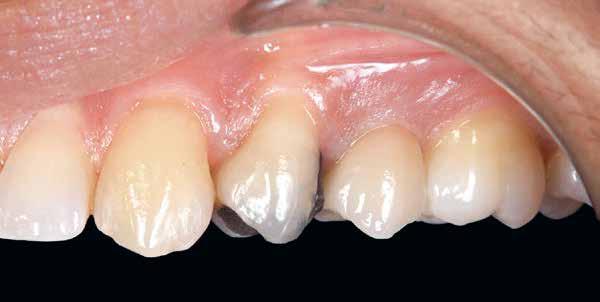

12. b. ábra: Okkluzális nézet négy hónappal a műtét után, amely megfelelő bukkális lágyszövetvastagságot mutat.

13. ábra: Négy hónap elteltével a szájüregben látható marginális zenit megmaradt.

14. ábra: Egészséges implantátum körüli lágyrészgallér.

uni.fit titánalapra (bredent medical). Az implantátum körül a bukkális lágyszövet megfelelő vastagságot és kedvező ínykontúrt mutatott (12. a–b. ábra). Az egyedi ínyformázó eltávolítása után egészséges implantátum körüli lágyrészgallér

volt megfigyelhető (13–14. ábra), ezen kívül közvetlenül a műtét előtt intraorális vizsgálatot végeztünk a lágyszöveti profil megállapítása érdekében. Ezt követte a scanbody behelyezése, így digitális lenyomat készült az implantátum pozíciójáról (15. ábra). Ugyanezzel a technikával rögzítettük az antagonista fogívet és a harapást is. Az így kapott STL-fájlokat digitálisan továbbítottuk a fogtechnikai laboratóriumba. A titánalapra PMMA ideiglenes koronát készítettünk a proximális és marginális illeszkedés ellenőrzése érdekében, valamint a megfelelő harapás elérése céljából (16–17. ábra) Miután az összes igazítás elkészült, ismételt vizsgálatot végeztünk. A végleges hibrid csavarrögzítésű, teljes kontúrú cirkóniumkoronát titánalapon erősen polírozott szubgingivális résszel készítettük el, és 25 Ncm nyomatékra húztuk (18. ábra). Kiváló árnyalategyezést és klinikai eredményt